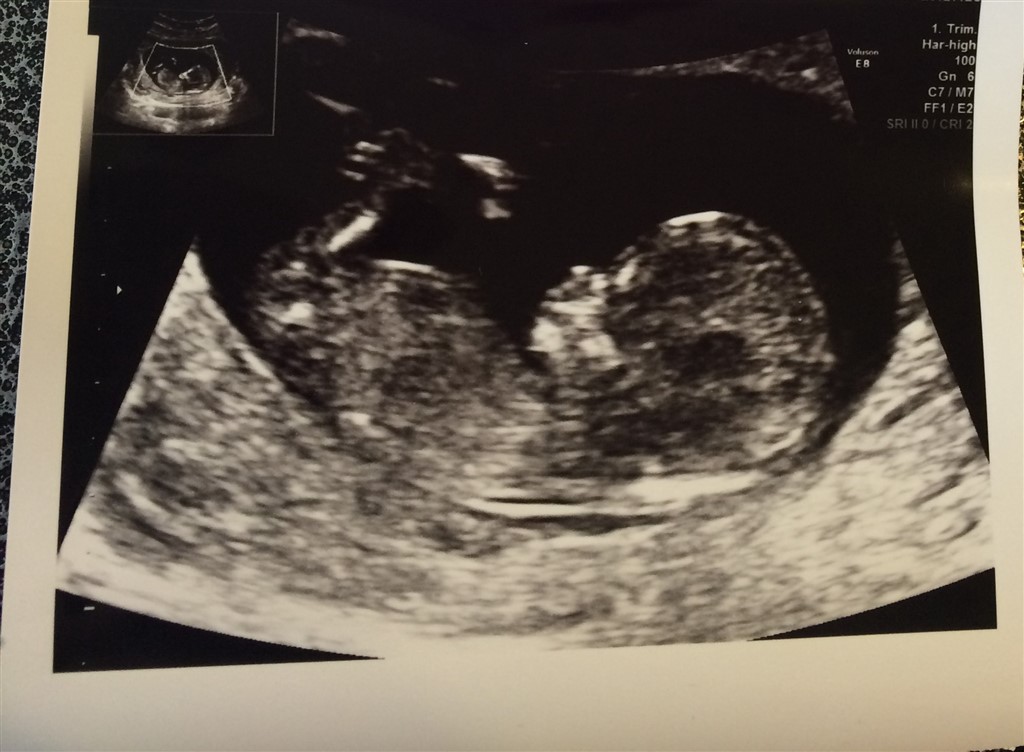

Så er NF scanningen veloverstået!

Jeg har en livlig lille baby inde i maven og med lav risiko, så alt er som det skal være

Næste scanning er kønsscanning, glæder mig til at se om den bette bliver ved med at ligne en pige